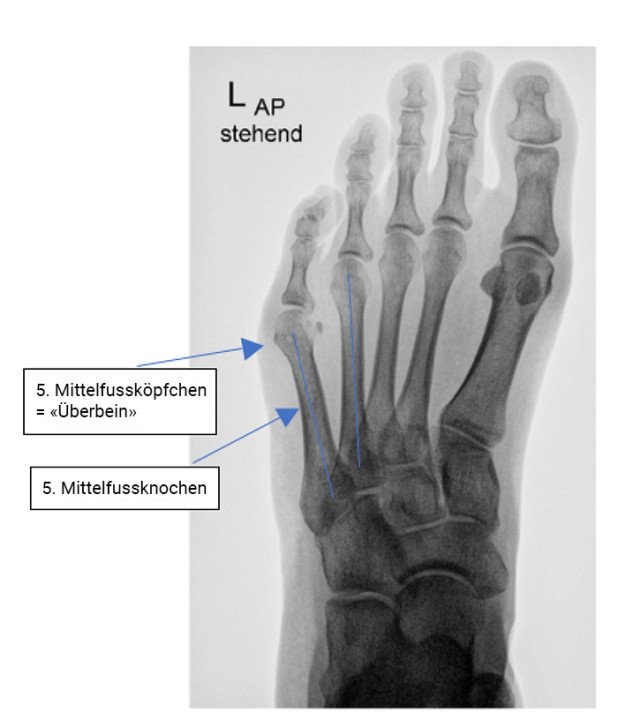

Zustand nach Abtragung des «Überbeines»

Abb. 2: Zustand nach Abtragung des «Überbeines»

Die Ursache dieser spezifischen Beschwerden ist nicht die Entwicklung eines vermeintlichen Überbeins, sondern vielmehr eine zunehmende Fehlstellung des 5. Mittelfussknochens «nach aussen». Das «Überbein» entspricht einer ganz normalen anatomischen Struktur, nämlich dem 5. Mittelfussköpfchen. Demzufolge ist es ein Fehler, dieses «Überbein» abzutragen, auch wenn dies als einfachste Lösung nahegelegt wird. Vielmehr muss der 5. Mittelfussknochen, der eine wichtige tragende Funktion hat, nach «innen» gerichtet werden, um ihm seine normale anatomische Stellung wiederzugeben.

Unsere Patientin hatte nach der oben erwähnten Operation mit alleiniger Abtragung des «Überbeines» stärkere Beschwerden als vor dem Eingriff. Die Operationsnarbe hatte sich schmerzhaft verdickt, was das Tragen von engeren Schuhen unmöglich machte. Ihre kleine Zehe fühlte sich wie «leblos» an, hatte ausserdem keinen Bodenkontakt mehr.  Dies alles wirkte sich behindernd im Alltag bei der Ausübung sportlicher Aktivitäten aus.